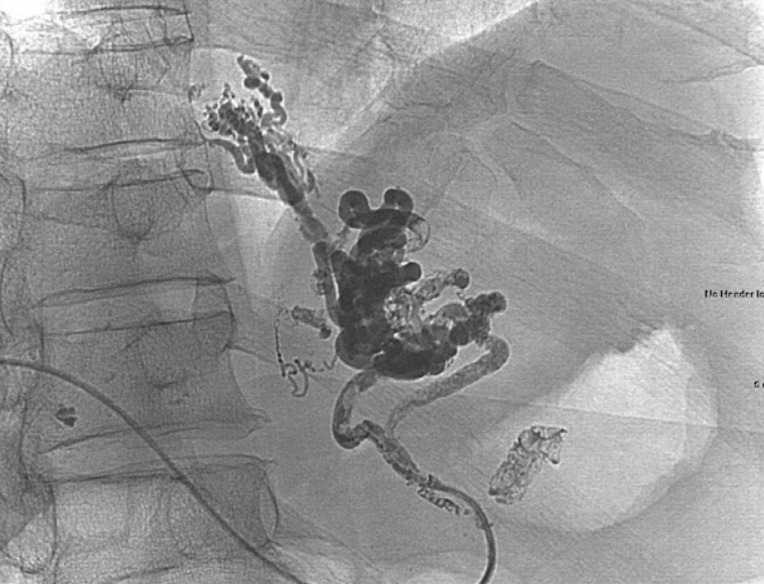

Fig. 1

Enhanced CT scan demonstrates gastric cardiac varices (arrow).